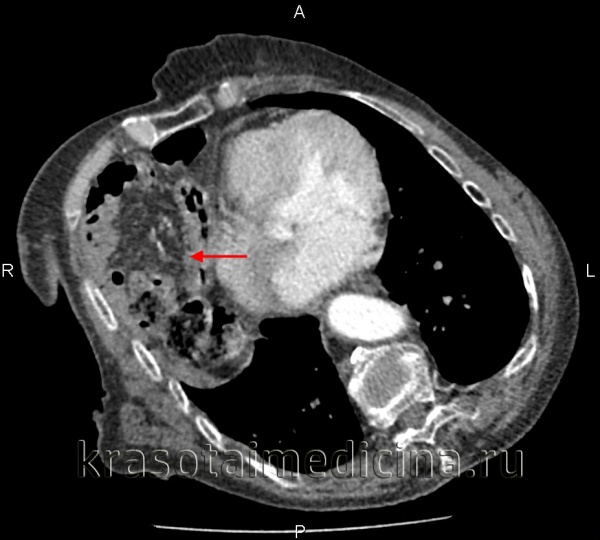

(Слева) На аксиальной КТ с контрастным усилением у молодого мужчины, пострадавшего в ДТП, определяется разрыв паренхимы селезенки с наличием сгустка крови высокой плотности, прилежащего к ее краю.

(Справа) На аксиальной КТ с контрастным усилением у этого же пациента также определяется сгусток крови, прилежащий к краю селезенки (типичный «сторожевой сгусток»), наряду со скоплением геморрагической жидкости меньшей плотности, более однородной структуры, во всех отделах брюшной полости. Заживление произошло самостоятельно, без хирургического вмешательства.